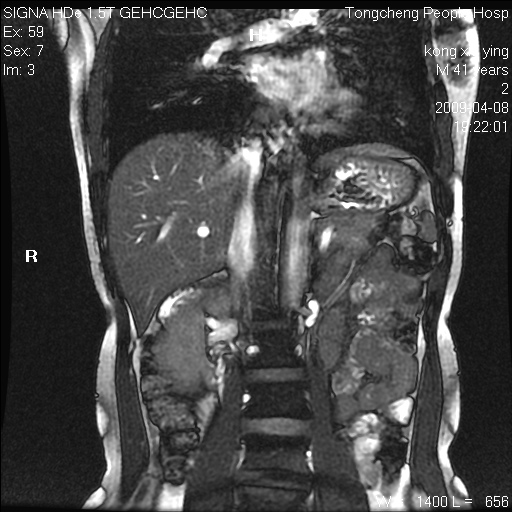

标题: CL1008:【经典】胆囊石榴籽样结石。

女,41岁。健康体检——彩超提示:胆囊显示不清。平素健康,无不适感。

腹部mr扫描及mrcp,图像如下: